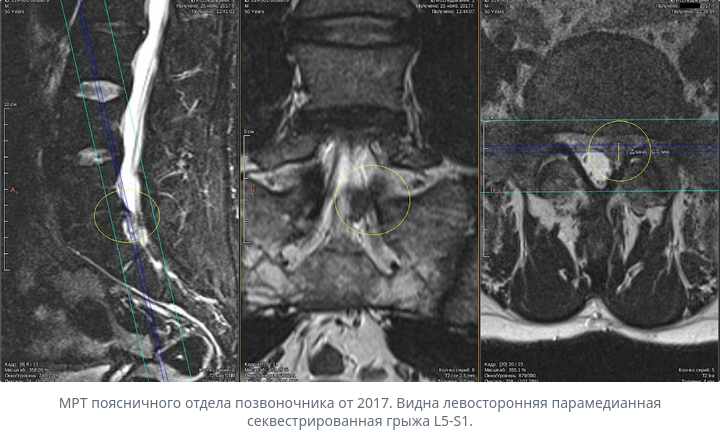

Хорошая новость: грыжа межпозвоночного диска часто сама рассасывается без операции. Организм воспринимает выпячивание диска как инородное тело и постепенно его разрушает и выводит. Это называется резорбция (от слова «рассасывание»).

Такое рассасывание происходит у 70–77% пациентов, которые придерживаются консервативного лечения (без операции). Для крупных грыж, которые отделились и выступают в спинномозговой канал, вероятность ещё выше — до 96%.

На снимке МРТ этот процесс можно увидеть по кольцевидному усилению сигнала вокруг грыжи — это видны кровеносные сосуды, которые прорастают в грыжу.

- Большой размер грыжи (парадоксально, но крупные грыжи часто рассасываются быстрее, так как лучше контактируют с кровеносными сосудами).

- Полный разрыв оболочки диска — это помогает сосудам и иммунным клеткам достичь грыжи.

- Интенсивное кровоснабжение вокруг грыжи (видно на МРТ).